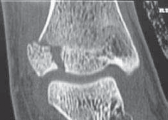

11. If there is any suspicion of an ankle injury, a complete plain radiographic ankle series should be performed. This consists of anteroposterior (AP), lateral, and mortise views (

FIG 2A–C

).

FIG 2•

Triplane fracture imaging. All ankle fractures require a plain radiographic series comprising AP (

A

), lateral (

B

), and mortise views (

C

D–G.

Three-dimensional CT reconstructions can aid in operative planning, especially for the difficult-to-

F G visualize intra-articular fractures.

4. Computed tomography (CT) is required to fully understand many ankle fractures, and we often advocate three-dimensional postreduction CT scans (

FIG 2D–G

1. We advocate CT scans for intra-articular fractures that show any evidence of displacement on plain radiographs, and we routinely obtain three-dimensional CT scans for triplane and many Tillaux fractures after attempted closed reduction.

2. For any physeal fracture with apparent displacement in children with greater than 2 years of growth remaining, we advocate CT scanning of the ankle to evaluate for displacement, as we recommend operative treatment for trapped periosteum with greater than 2 mm of displacement.